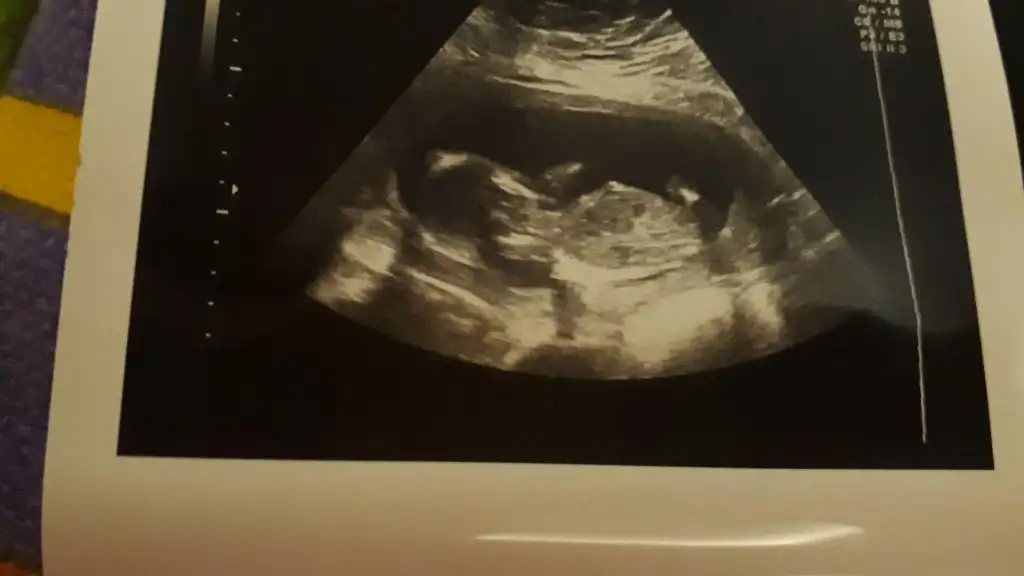

17 haftalıktekrar atarsınız demiştiniz bu sefer sanki daha belirgin tahmininizi alabilirmiyim ❣ Ikra meyra

Erkek görünüyor

Evet yaa biraz üstte oluyor demekki 17+ da pipi olusunca az önce bu gördüğüm pipi ise tabikiTeşekkür ederim benimde gönlüm kız hep öyle hissetim ama erkek dedi doktorum bugün değişirmi bilmiyorumçok teşekkür ederim cevabınız için

Aaa siz işaretleyince gördüm bugün bana 4 kere gösterdi görmüyormusun şekerim pipi bu pipi kız yok dedi doktorEvet yaa biraz üstte oluyor demekki 17+ da pipi olusunca az önce bu gördüğüm pipi ise tabiki